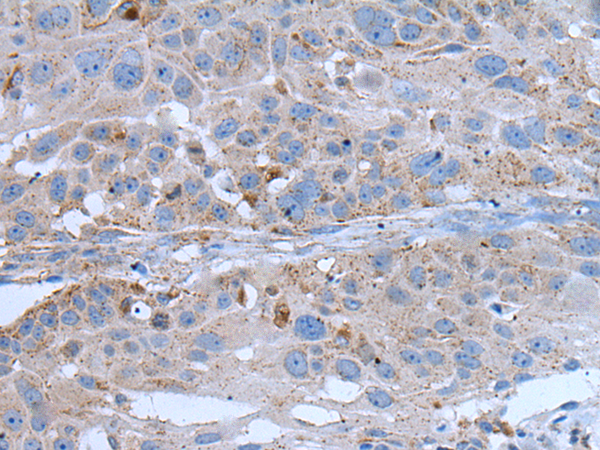

分类: 科研抗体货号: P12860别名:应用: IHC反应种属: Human, Mouse